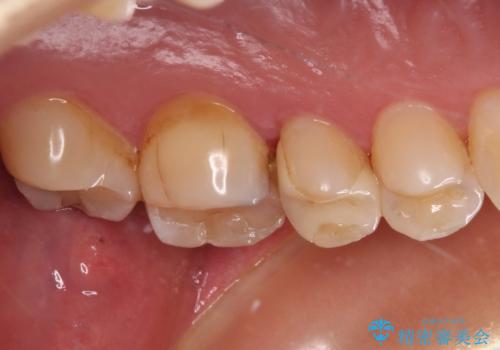

根管治療を行った奥歯は、再発防止や残された歯質を守るため、クラウンによる補綴治療が必要となります。

補綴後数ヶ月経過しレントゲンを撮影したところ、根尖周辺の病変が消退してきていることが確認できました。